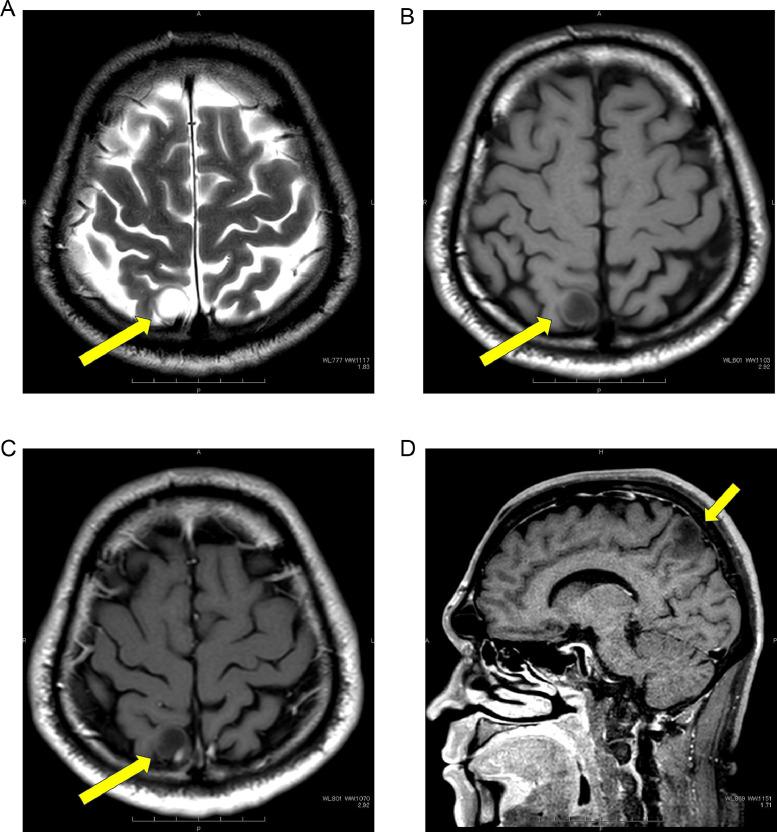

Thoracic -deficient undifferentiated tumor (-UT) is characterized by an undifferentiated rhabdoid morphology and deficiency pathologically. In the 2021 revision of the WHO classification, it was categorized as an epithelial tumor because of its shared genetic background with smoking-related lung cancer. We describe the case of a 44-year-old man with a rapidly enlarging mediastinal mass observed on chest radiography and CT. The tumor was resistant to radiation therapy, chemotherapy, and immune checkpoint inhibitors, and the patient's survival time was approximately 5 months. Familiarity with the clinical background and imaging findings of thoracic -UT is crucial for early diagnosis and treatment planning.

胸段发育不全未分化肿瘤(-UT)的特征是具有未分化的横纹肌样形态且病理表现为发育不全。在世界卫生组织(WHO)2021年的分类修订版中,因其与吸烟相关肺癌具有共同的遗传背景,它被归类为上皮性肿瘤。我们描述了一名44岁男性的病例,胸部X线和CT检查发现其纵隔肿块迅速增大。该肿瘤对放射治疗、化疗和免疫检查点抑制剂均耐药,患者生存时间约为5个月。熟悉胸段-UT的临床背景和影像学表现对于早期诊断和治疗规划至关重要。